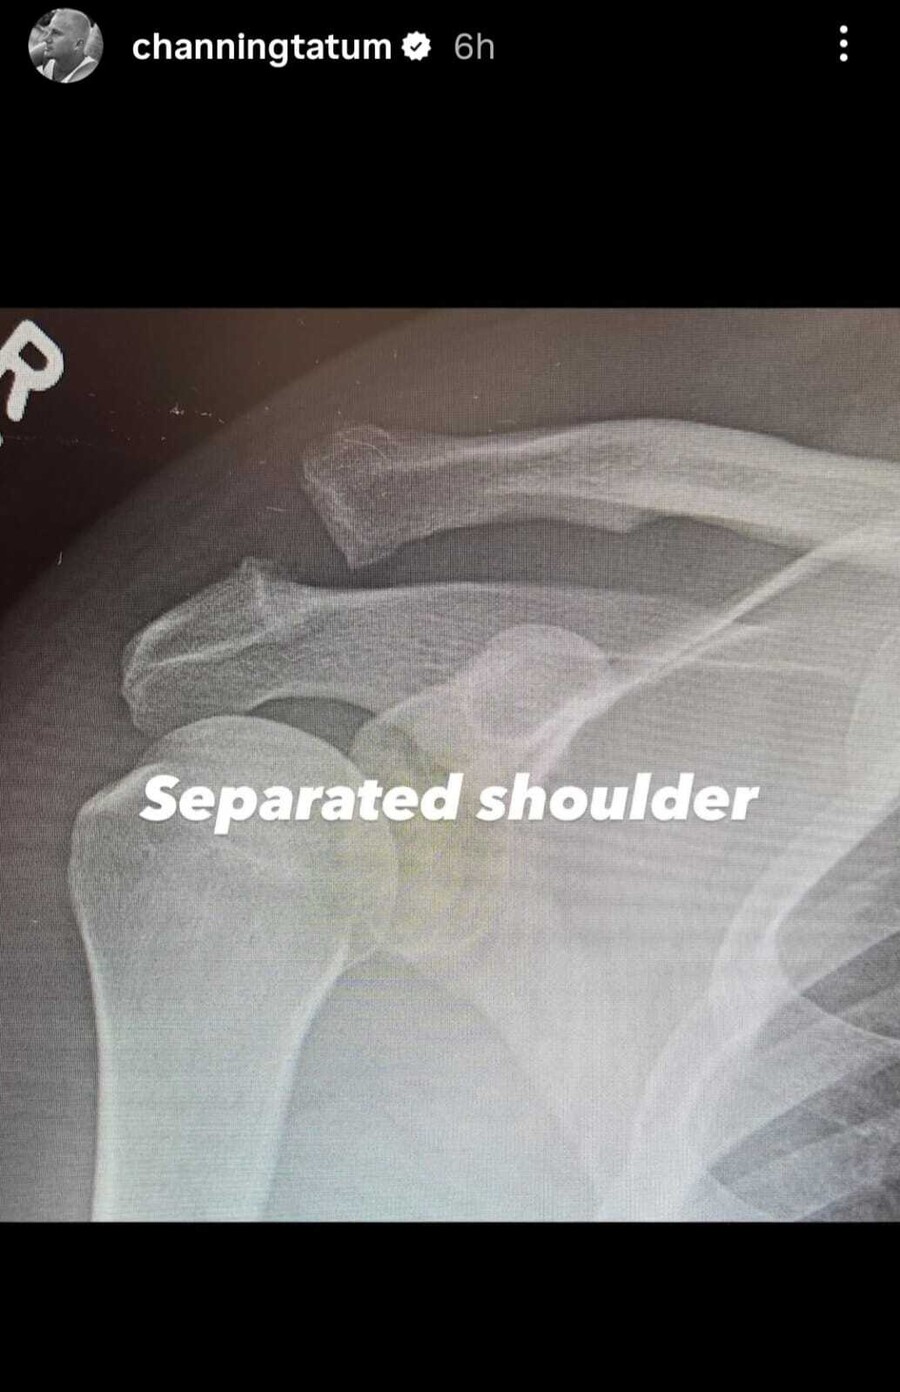

Ο αγαπημένος ηθοποιός του Hollywood, Channing Tatum, βρέθηκε σήμερα στο νοσοκομείο, όπου υποβλήθηκε σε επέμβαση στον ώμο έπειτα από σοβαρό τραυματισμό. Ο ίδιος αποκάλυψε το περιστατικό μέσα από ανάρτησή του στα social media, όπου μοιράστηκε φωτογραφίες από το κρεβάτι του νοσοκομείου αλλά και ακτινογραφίες του ώμου του πριν και μετά την επέμβαση.

Στις εικόνες φαίνεται καθαρά ότι ο Tatum υπέστη διαχωρισμό ή εξάρθρωση ώμου (separated shoulder), με τους γιατρούς να τοποθετούν βίδα για να σταθεροποιήσουν την άρθρωση. Με χιούμορ, ο ηθοποιός έγραψε στη λεζάντα πως κυριολεκτικά έχει πλέον έναν «screwed shoulder» που είναι ένα λογοπαίγνιο σε αργκο για την κυριολεκτική βίδα που μπήκε στον ώμο του.